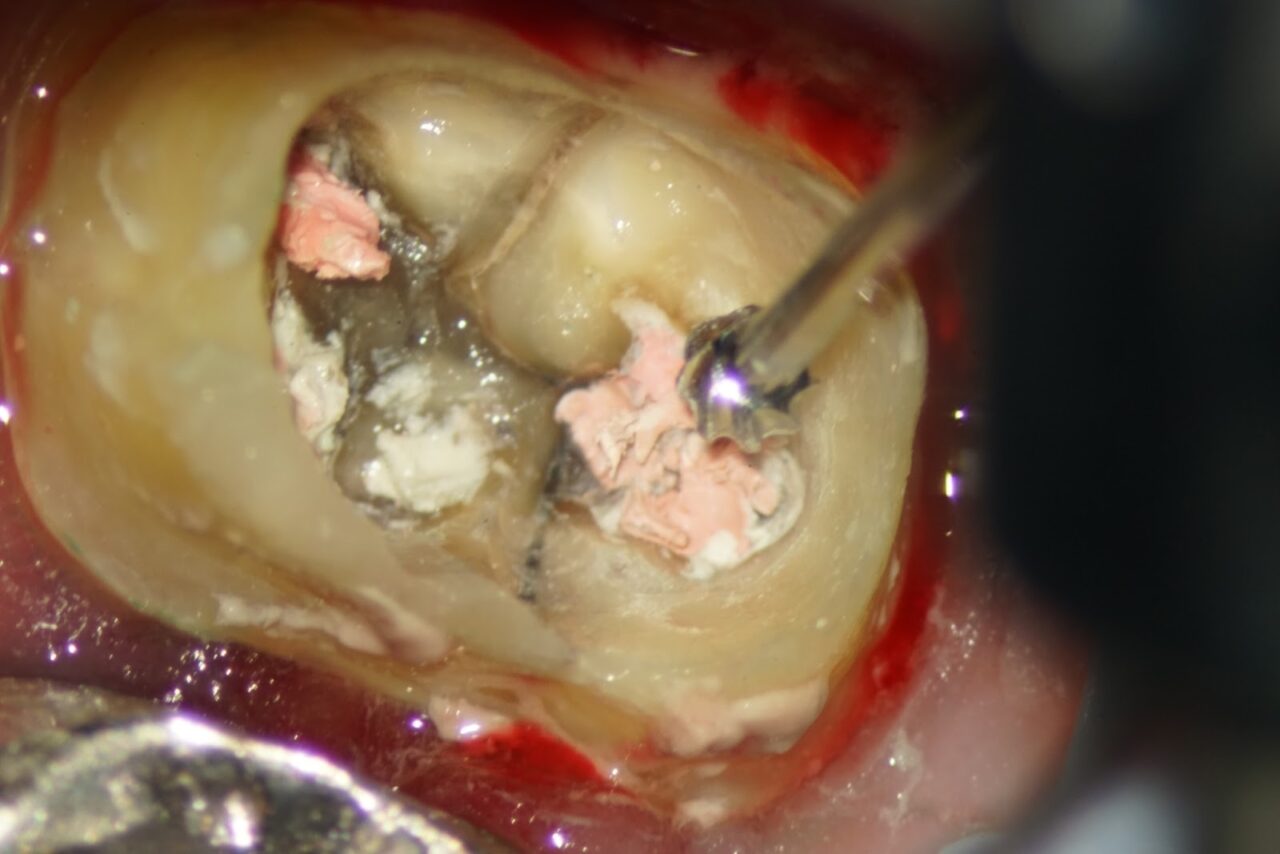

麻酔をした後にラバーダム防湿を行い、ジルコニアと思われるクラウンを外します。

クラウンを外すとレジンコアが入っており、少し削ると感染して変色した破折線が確認されました。

根管内の古い充填物を除去していくと近遠心に繋がる破折線がより明確に成ってきました。

一般的な治療、大学病院やアメリカ帰りの歯科医師では破折線が確認された時点で抜歯の診断基準を満たしており、抜歯と診断され、この時点で治療終了になります。

吉松歯科医院では、破折歯の治療を15年以上前から続けており、15年を超える症例もあります。

感染部が緑色に染まるう蝕検知液で、感染部の除去を徹底して行います。

以前の根管内の充填物が除去する事が出来たので、破折線の感染除去を行います。

破折線を可能な限り細い器具で感染部を除去して行きます。

破折線の処理がほとんど終わった状態です、少し前の写真と比べるとキレイに成っている事が確認できます。

スーパーボンドという日本製の接着剤を用いて破折の接着を行います。

その後にフローレジンにて歯の強度を高めるために隔壁を兼ねたレジン隔壁を作ります。

次回より本格的な根管治療を行うための準備をしました。CTで根管の内容物がきちんと取り除かれている事が確認できれば、次回はバイオセラミックを用いた根管充填になります。